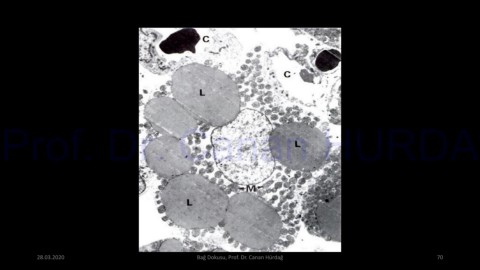

Page 70 - BAĞ DOKUSU